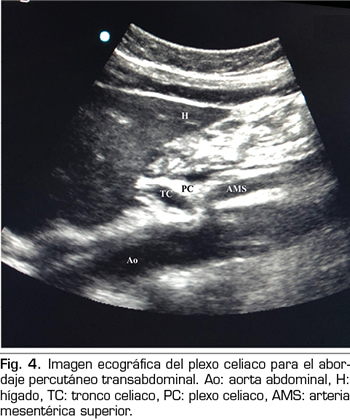

NEURÓLISIS PERCUTÁNEA ECOGRÁFICA DEL PLEXO CELIACO

En los últimos años la ecografía ha ido ganando terreno a la fluoroscopia y al TAC en el manejo intervencionista del dolor. El primero en describir la técnica sobre el plexo celiaco fue Bhatnagar (31), pudiendo ser realizada percutáneamente en la cabecera del paciente y en decúbito supino, lo que da mayor comodidad tanto para el paciente como para el médico. Sin embargo, todavía no existen ensayos controlados y aleatorizados que comparen la neurólisis ecográfica abdominal del plexo celiaco frente al tratamiento sistémico opioide. La técnica se realiza utilizando una sonda convex (2-5 MHz), colocada inicialmente justo por debajo de la apófisis xifoides en el plano transversal, para identificar estructuras como hígado, estómago, intestino, venas portales, cava y aorta. Con la ayuda del Doppler, escaneamos caudalmente para identificar la bifurcación del tronco celiaco en las arterias hepática y esplénica, y más distalmente en la arteria mesentérica superior. Es entonces cuando giramos el transductor en el plano longitudinal, visualizando en la misma imagen la bifurcación de la aorta en el tronco celiaco y en la arteria mesentérica superior con el plexo celiaco rodeando estas estructuras. El abordaje se realiza en plano, transabdominal, atravesando el hígado o el estómago, siempre y cuando no haya grandes vasos interfiriendo el recorrido de la aguja (Figura 4).

No se han reportado complicaciones con el abordaje percutáneo ecográfico; de todas formas, la literatura al respecto es insuficiente como para extraer conclusiones (32).